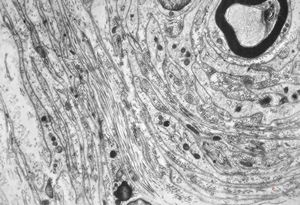

F,23y. | - n.suralis- hypertrophic demyelinizing neuropathy (onion bulbs)

F,23y. | - n.suralis- hypertrophic demyelinizing neuropathy (onion bulbs)